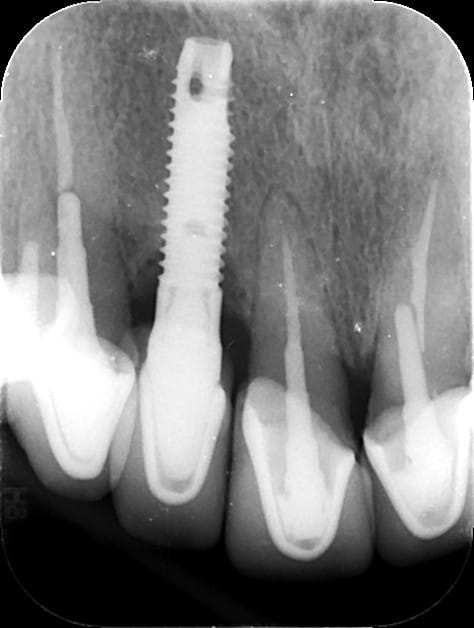

pour une fois, j'ai besoin de vous....enfin des plus anciens nonoliens poseurs de clous....

cet implant à été posé il y a plus de 20 ans (voir 30....) ainsi que ces petits copains mandibulaires....et justement le bas est à refaire, mais ce cliché est le plus mieux bien pour une identification....

si vous avez croisés ce type d'implant et que vous vous souvenez de ce que c'est, çà m'aiderais.....car pour l'instant, je n'ai rien trouvé dans tous les moteurs de recherche implantaire que je connais....

dans les caractéristiques, il y a ces trous apicaux....

Avec cette connexion interne???? je n'y crois pas...on dirait plus une connexion type 3i....mais jamais vu avec une zone apicale comme çà

Le branemark MKI avait un apex très ressemblant tout de même.

Pour la connection, pas évident de dire si c’est interne ou externe. C’est une latérale, donc probablement un implant narrow . Ça complique l’identification de la connection.

Non Olieve, c’est pas ça....impossible

Mais bon, comme il faut toujours compter que sur soit même...je l’ai finalement trouvé cet implant préhistorique 😂

C’est un vieux Serf EVL qui n’avait pas encore les microspires au col....comme sur l’EVL N que je connais

https://www.spotimplant.com/fr/implants-dentaire/serf-implanter-innovation/serf-implant-evl